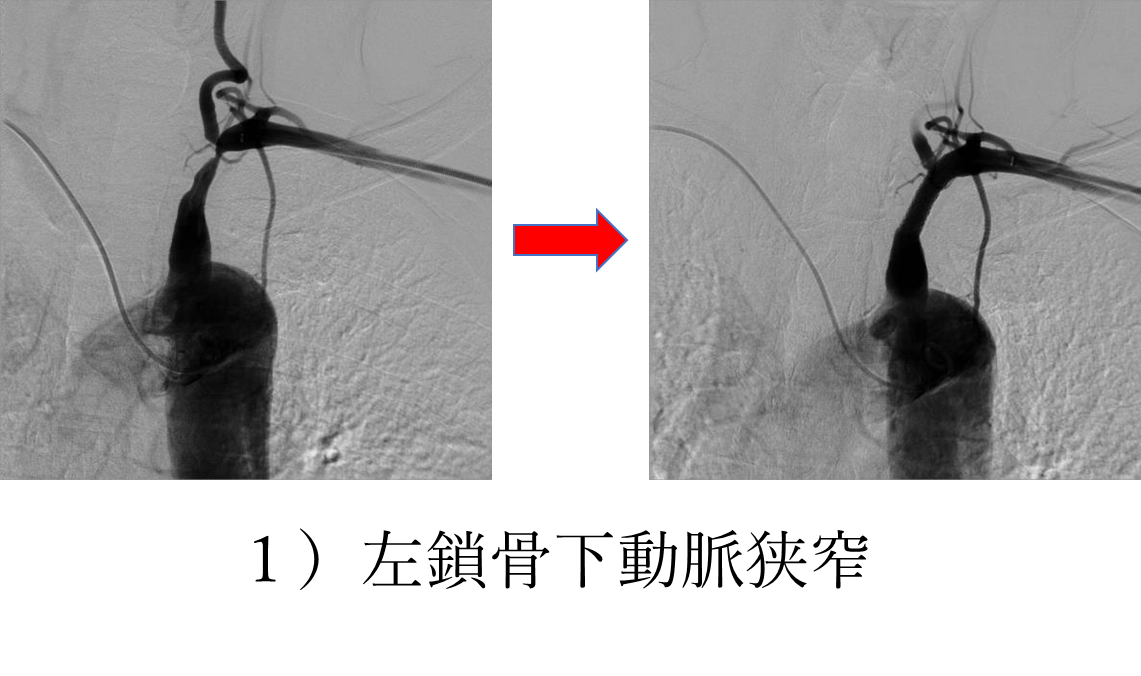

下にいくつかの症例を提示いたしますが、末梢動脈疾患も例えば1)の左鎖骨下動脈狭窄症の方はシャンプーをするときに左腕がだるくて洗い続けることができず、血圧の左右差を認めているということで御紹介いただいた方の治療前後の画像となります。